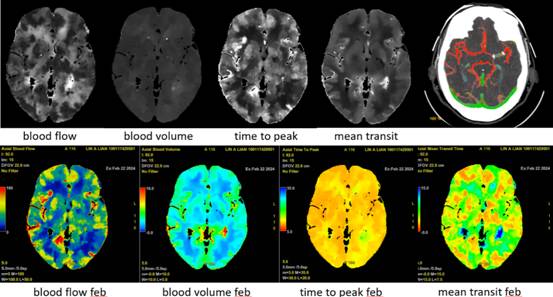

2、脑卒中一站式完成多期扫描

Apex CT通过DLIR技术,突破以往CT需要多次打药、多次扫描的弊端,实现一次对比剂注射下得到CTA、CTV、灌注等临床所需图像,极大缩短抢救患者检查时间。